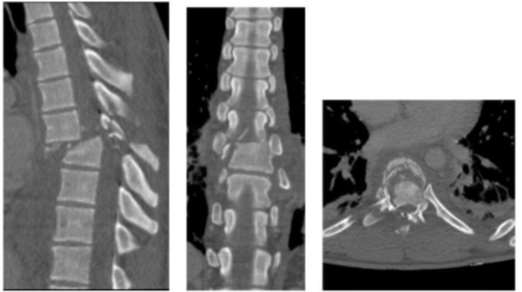

Foram realizadas TCs, sendo a de crânio normal e a de toda a coluna com os seguintes achados anormais: